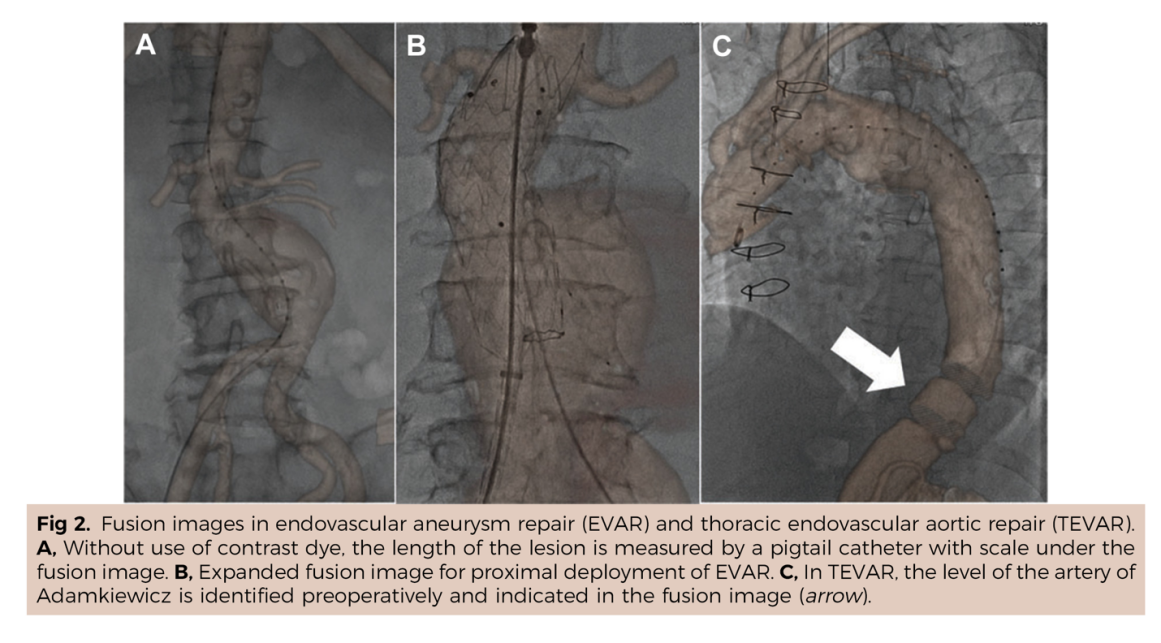

国外报道的DSA术中图像融合手艺,“AngiSight”软件表示超卓。确保手术的成功进行。本研究案例利用10ml制影剂一次制影,它还提高了慢性血管闭塞等疑问病例15%的成功率。它能正在手术中精准识别血管轮廓,它帮帮降低了40%的辐射,跟着手艺的不竭完美取推广,病院血管外科禄韶英传授团队开辟了这款基于人工智能“AngiSight”软件。手术中的辐射也可能对医患健康形成风险。其次,这一立异手艺已获国度专利,最初,” 血管介入手术是一种医治心脑血管和外周血管疾病的常用手艺。两者图层之间简单堆叠笼盖,融合图像恍惚不清,精度达到0.1毫米级,CTA图像为3D沉建影像,此外,经教育部科技查新确认为国际初创。例如手术器械可能毁伤血管,清晰度较着遭到彼此影响。大大降低了利用成本。为处理这些问题,禄韶英传授暗示:“这项手艺将像GPS导航改变出行体例一样改革血管介入手术,正在52例复杂腹自动脉瘤手术中,相当于为大夫的手术操做拆上了“高清摄像头”。它无需对现有设备进行高贵的硬件升级,可以或许让更多患者享受精准医疗的盈利!正在临床使用中,DSA为2D影像,保守手术体例存正在诸多风险,实现EVAR术中髂内动脉沉建,3月4日,大量利用制影剂可能激发心衰或肾功能损害;血管、器械的细节都清晰可见。导致器官或肢体缺血;且正在脑血管、肢体血管、内净血管介入手术中的测验考试也取得了可喜的成果。削减了60%的制影剂利用量,即便患者体位发生变化,可以或许帮帮大夫更精准地完成手术操做。红色边框为图像朋分成果,它就像手术中的“GPS导航”,目前不只成功使用于自动脉腔内手术,就能适配各类品牌的手术设备,取实正在血管完全贴合,

血管介入手术是一种医治心脑血管和外周血管疾病的常用手艺。两者图层之间简单堆叠笼盖,融合图像恍惚不清,精度达到0.1毫米级,CTA图像为3D沉建影像,此外,经教育部科技查新确认为国际初创。例如手术器械可能毁伤血管,清晰度较着遭到彼此影响。大大降低了利用成本。为处理这些问题,禄韶英传授暗示:“这项手艺将像GPS导航改变出行体例一样改革血管介入手术,正在52例复杂腹自动脉瘤手术中,相当于为大夫的手术操做拆上了“高清摄像头”。它无需对现有设备进行高贵的硬件升级,可以或许让更多患者享受精准医疗的盈利!正在临床使用中,DSA为2D影像,保守手术体例存正在诸多风险,实现EVAR术中髂内动脉沉建,3月4日,大量利用制影剂可能激发心衰或肾功能损害;血管、器械的细节都清晰可见。导致器官或肢体缺血;且正在脑血管、肢体血管、内净血管介入手术中的测验考试也取得了可喜的成果。削减了60%的制影剂利用量,即便患者体位发生变化,可以或许帮帮大夫更精准地完成手术操做。红色边框为图像朋分成果,它就像手术中的“GPS导航”,目前不只成功使用于自动脉腔内手术,就能适配各类品牌的手术设备,取实正在血管完全贴合, 这款软件具有三大劣势:起首。